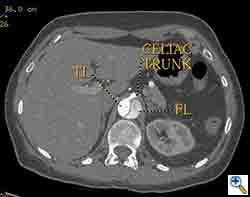

The patient was taken to the hybrid operating suite and a thoracic aortogram was performed. The aortogram confirmed the chronic Type B aortic dissection with a patent false lumen and a fenestration just beyond the left subclavian artery. An intravascular ultrasound (IVUS) was also performed of the entire aortic arch and descending thoracic and abdominal aorta. The IVUS also confirmed that there was an adequate proximal landing zone beyond the left subclavian artery consisting of normal aorta where we would be able to achieve adequate seal of the endovascular stent graft. The septal fenestration began approximately 1.5 cm distal to the left subclavian artery. The true lumen was compressed distally. (Figure 2) The celiac artery appeared to come off the true lumen. (Figure 3) The dissection extended into the superior mesenteric artery and the artery was perfused from both the true and false lumen. (Figure 4) The left renal artery came off the false lumen. (Figure 5) The right renal artery came off the true lumen.